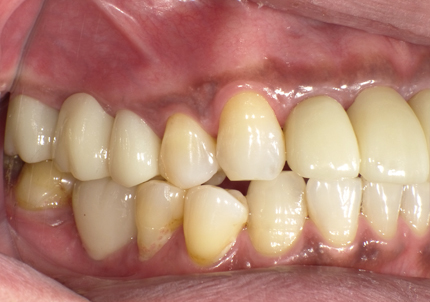

10.口腔内写真(2022年2月)

特に問題無く経過はとても良いです。

患者様ご本人も「良く咬めてとても良い」と満足されています。

11.口腔内写真(2025年6月)

右下2本初診より9年経過、左下3本埋入後4年経過、ともに経過良好。